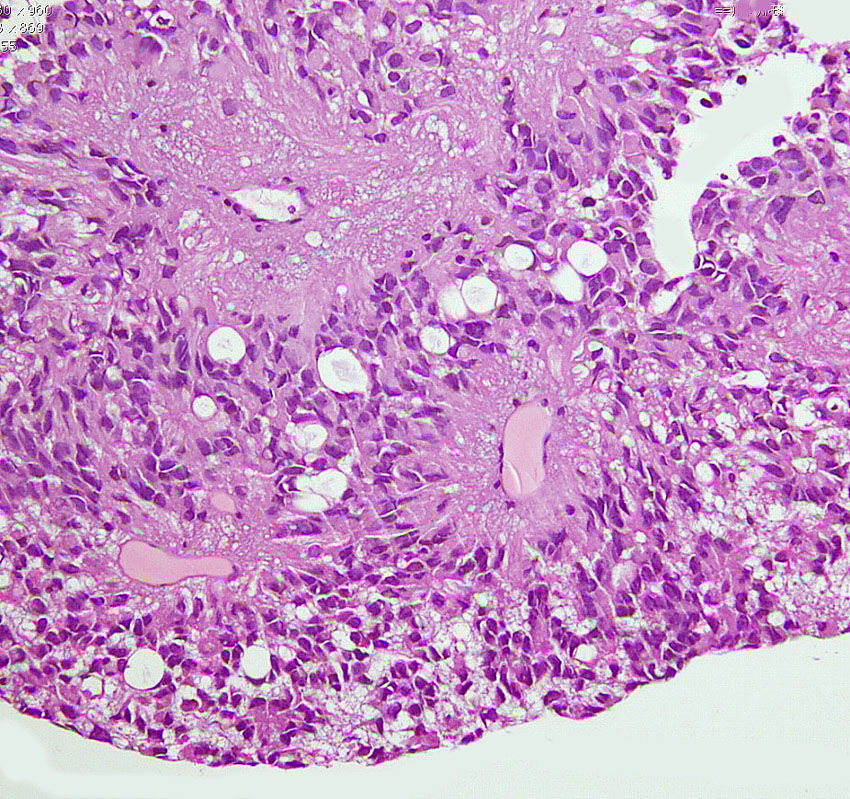

第4脳室床に発生した典型的な上衣腫 EPN-PFA の画像です。水頭症になって,頭痛と嘔吐,意識障害で発症しました。典型的なMRI画像と病理所見です。MRIでは第4脳室からマジャンディー孔を越えて脊髄背側まで長く腫瘍が伸びています。腫瘍内部に小さなのう胞が複数みられます。病理像では,血管周囲に細胞核がない無核野が認められます。血管周囲に伸びた繊細な単極性突起が集まった領域です。これは,血管周囲偽ロゼット perivascular pseudorosette という上衣腫に特徴的な病理所見です。

グレード2の組織像です。血管周囲に無核野があり,腫瘍の核は血管から離れているパターンが特長です。perivascular pseudo-rosetteといいます。